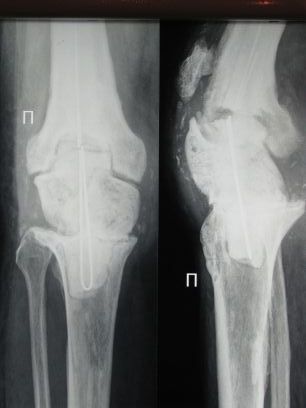

Последствие эндопротезирования

Пациент 69 лет.С 2002 года пережил три эндопротеза правого коленного сустава. В ноябре 2008 года эндопротез удален, дефект заполнен спейсером. В ноябре же был эпизод воспаления в области надколенника.

Задача на момент поступления - создать опорную ногу за короткий промежуток времени.